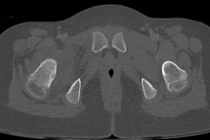

Cứu đôi chân cho bệnh nhi 7 tuổi bị u xương hiếm gặp

Bệnh nhi là một bé gái 7 tuổi vốn khỏe mạnh bình thường cho đến khi xuất hiện những cơn đau dữ dội vùng đùi phải. Đặc biệt cơn đau tăng nặng vào ban đêm.

Bệnh viện Đại học Y Hà Nội một ca can thiệp ít xâm lấn hiếm gặp vừa được thực hiện thành công, mang lại hy vọng và niềm vui cho một gia đình sau chuỗi ngày dài bệnh nhân phải sống trong đau đớn và lo âu.

“Sau 6 tháng, hôm nay cháu mới có một giấc ngủ ngon như vậy… Gia đình cảm ơn các bác sĩ rất nhiều… Đọc tin nhắn từ người mẹ trẻ, mình như trút được một gánh nặng trong lòng”, TS.BS Nguyễn Ngọc Cương (Trưởng khoa Can thiệp điện quang, Bệnh viện Đại học Y Hà Nội) chia sẻ.